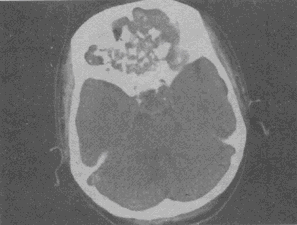

男,26岁,进行性鼻腔阻塞、流涕来院就诊,近两年持续性头痛、头晕,筛窦区病变影像检查如图,最可能的诊断是

A.脊索瘤伴左上颌窦炎

B.软骨瘤伴左上颌窦炎

C.骨化性纤维瘤伴左上颌窦炎

D.骨结核伴左上颌窦炎

E.骨纤维异常增殖症伴左上颌窦炎

男,26岁,进行性鼻腔阻塞、流涕来院就诊,近两年持续性头痛、头晕,筛窦区病变影像检查如图,最可能的诊断是<img border="0" style="width:

[单选题]男,26岁,进行性鼻腔阻塞、流涕来院就诊,近两年持续性头痛、头晕,筛窦区病变影像检查如图,最可能的诊断是A.脊索瘤伴左上颌窦炎B.软骨瘤伴左上颌窦炎C

男,26岁,进行性鼻腔阻塞、流涕来院就诊,近两年持续性头痛、头晕,筛窦区病变影像检查如图,最可能的诊断是()<img border="0" style="width

[单选题]男,26岁,进行性鼻腔阻塞、流涕来院就诊,近两年持续性头痛、头晕,筛窦区病变影像检查如图,最可能的诊断是()A.脊索瘤伴左上颌窦炎B.软骨瘤伴左上颌窦

男,26岁,进行性鼻腔阻塞、流涕来院就诊,近两年持续性头痛、头晕,筛窦区病变影像

[单选题]男,26岁,进行性鼻腔阻塞、流涕来院就诊,近两年持续性头痛、头晕,筛窦区病变影像检查如图,最可能的诊断是()A . 脊索瘤伴左上颌窦炎B . 软骨瘤伴左上颌窦炎C . 骨化性纤维瘤伴左上颌窦炎D . 骨结核伴左上颌窦炎E . 骨纤维异常增殖症伴左上颌窦炎

男,26岁,进行性鼻腔阻塞、流涕来院就诊,近两年持续性头痛、头晕,如图所示筛窦区

[单选题]男,26岁,进行性鼻腔阻塞、流涕来院就诊,近两年持续性头痛、头晕,如图所示筛窦区占位灶应诊断为()。A . 脊索瘤伴左上颌窦炎B . 软骨瘤伴左上颌窦炎C . 骨化性纤维瘤伴左上颌窦炎D . 骨结核伴左上颌窦炎E . 骨纤维异常增殖症伴左上颌窦炎

男,26岁,进行性鼻腔阻塞、流涕来院就诊,近两年持续性头痛、头晕.如图所示筛窦区

[单选题]男,26岁,进行性鼻腔阻塞、流涕来院就诊,近两年持续性头痛、头晕.如图所示筛窦区占位灶应诊断为()A .脊索瘤伴左上颌窦炎B .软骨瘤伴左上颌窦炎C .骨化性纤维瘤伴左上颌窦炎D .骨结核伴左上颌窦炎E .骨纤维异常增殖症伴左上颌窦炎